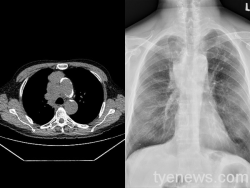

樂生療養院王琮柏:肺癌常無症狀盡早篩檢有利治療

64歲的李先生是退休的壓克力加工廠老闆,年輕時開始抽菸,也曾因為感染肺結核,接受過完整的治療。退休後在家人勸說下,定期接受健康檢查,但這兩年卻因疫情而不得不暫時中斷。最近疫情逐漸趨緩,重新進行全身健康檢查,經由低劑量胸部電腦斷層(LDCT)檢查,竟然發現縱膈腔及肋膜腫瘤,甚至已經侵犯到鄰近的大血管。 王琮柏醫院建議,年齡介於 50-80 歲、一年抽菸超過30包的老菸...... [閱讀更多]